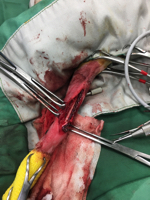

現在使用できるロッキングプレート&ネジの最小の物でギリギリです。

関節に近いところが折れているため大変です。

こちらの症例は2度目の骨折です。それも2回目の骨折でプレートがうまくはまっていなかったので今回ロッキングプレートにてやり直しました。